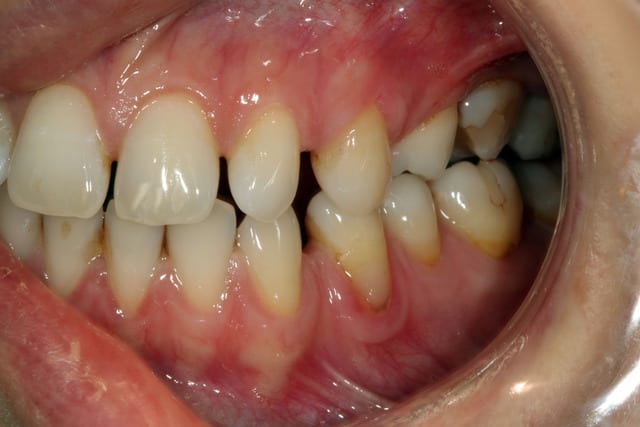

elle consulte pour une inflammation chronique secteur 2..

fermer les espaces antérieurs par ortho ou facette est aussi prévu..

Elles sont bien belles tes photos ;)

Si le patient se lance dans l'odf aucune raison de virer la 26.

Virer la 65, refermer les espaces en anterieur haut et bas ce qui permet d amener la 26 contre 24?

Si la 25 est asymptomatique pourquoi aller s .......der? Par contre si elle interfere dans le traitement ortho de rapprochement 26-24 alors oui.

Age du patient?

Salut aterman, je pense plutôt redresser la 26 pour me faire la place devant histoire de mettre une vis...

La patiente de 33 ans ( comme moi) n'ont pas forcément envie de virer 25 qui est complètement à symptomatique..